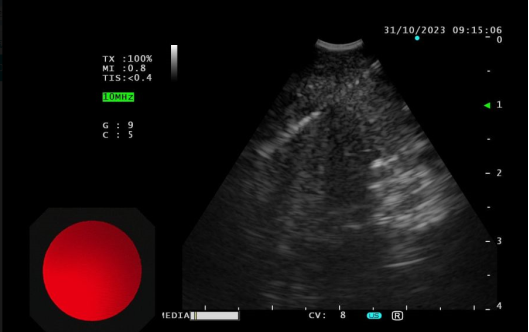

通过EBUS技术,医生能够在实时超声引导下,精确定位淋巴结并进行穿刺活检。通过这种方法的优势在于EBUS-TBNA的阳性率超过90%,能够有效区分良性和恶性病变。同时减少了对患者的创伤,避免了传统外科手术的风险。实时超声能够即时评估样本质量,确保获取足够的组织进行病理分析。